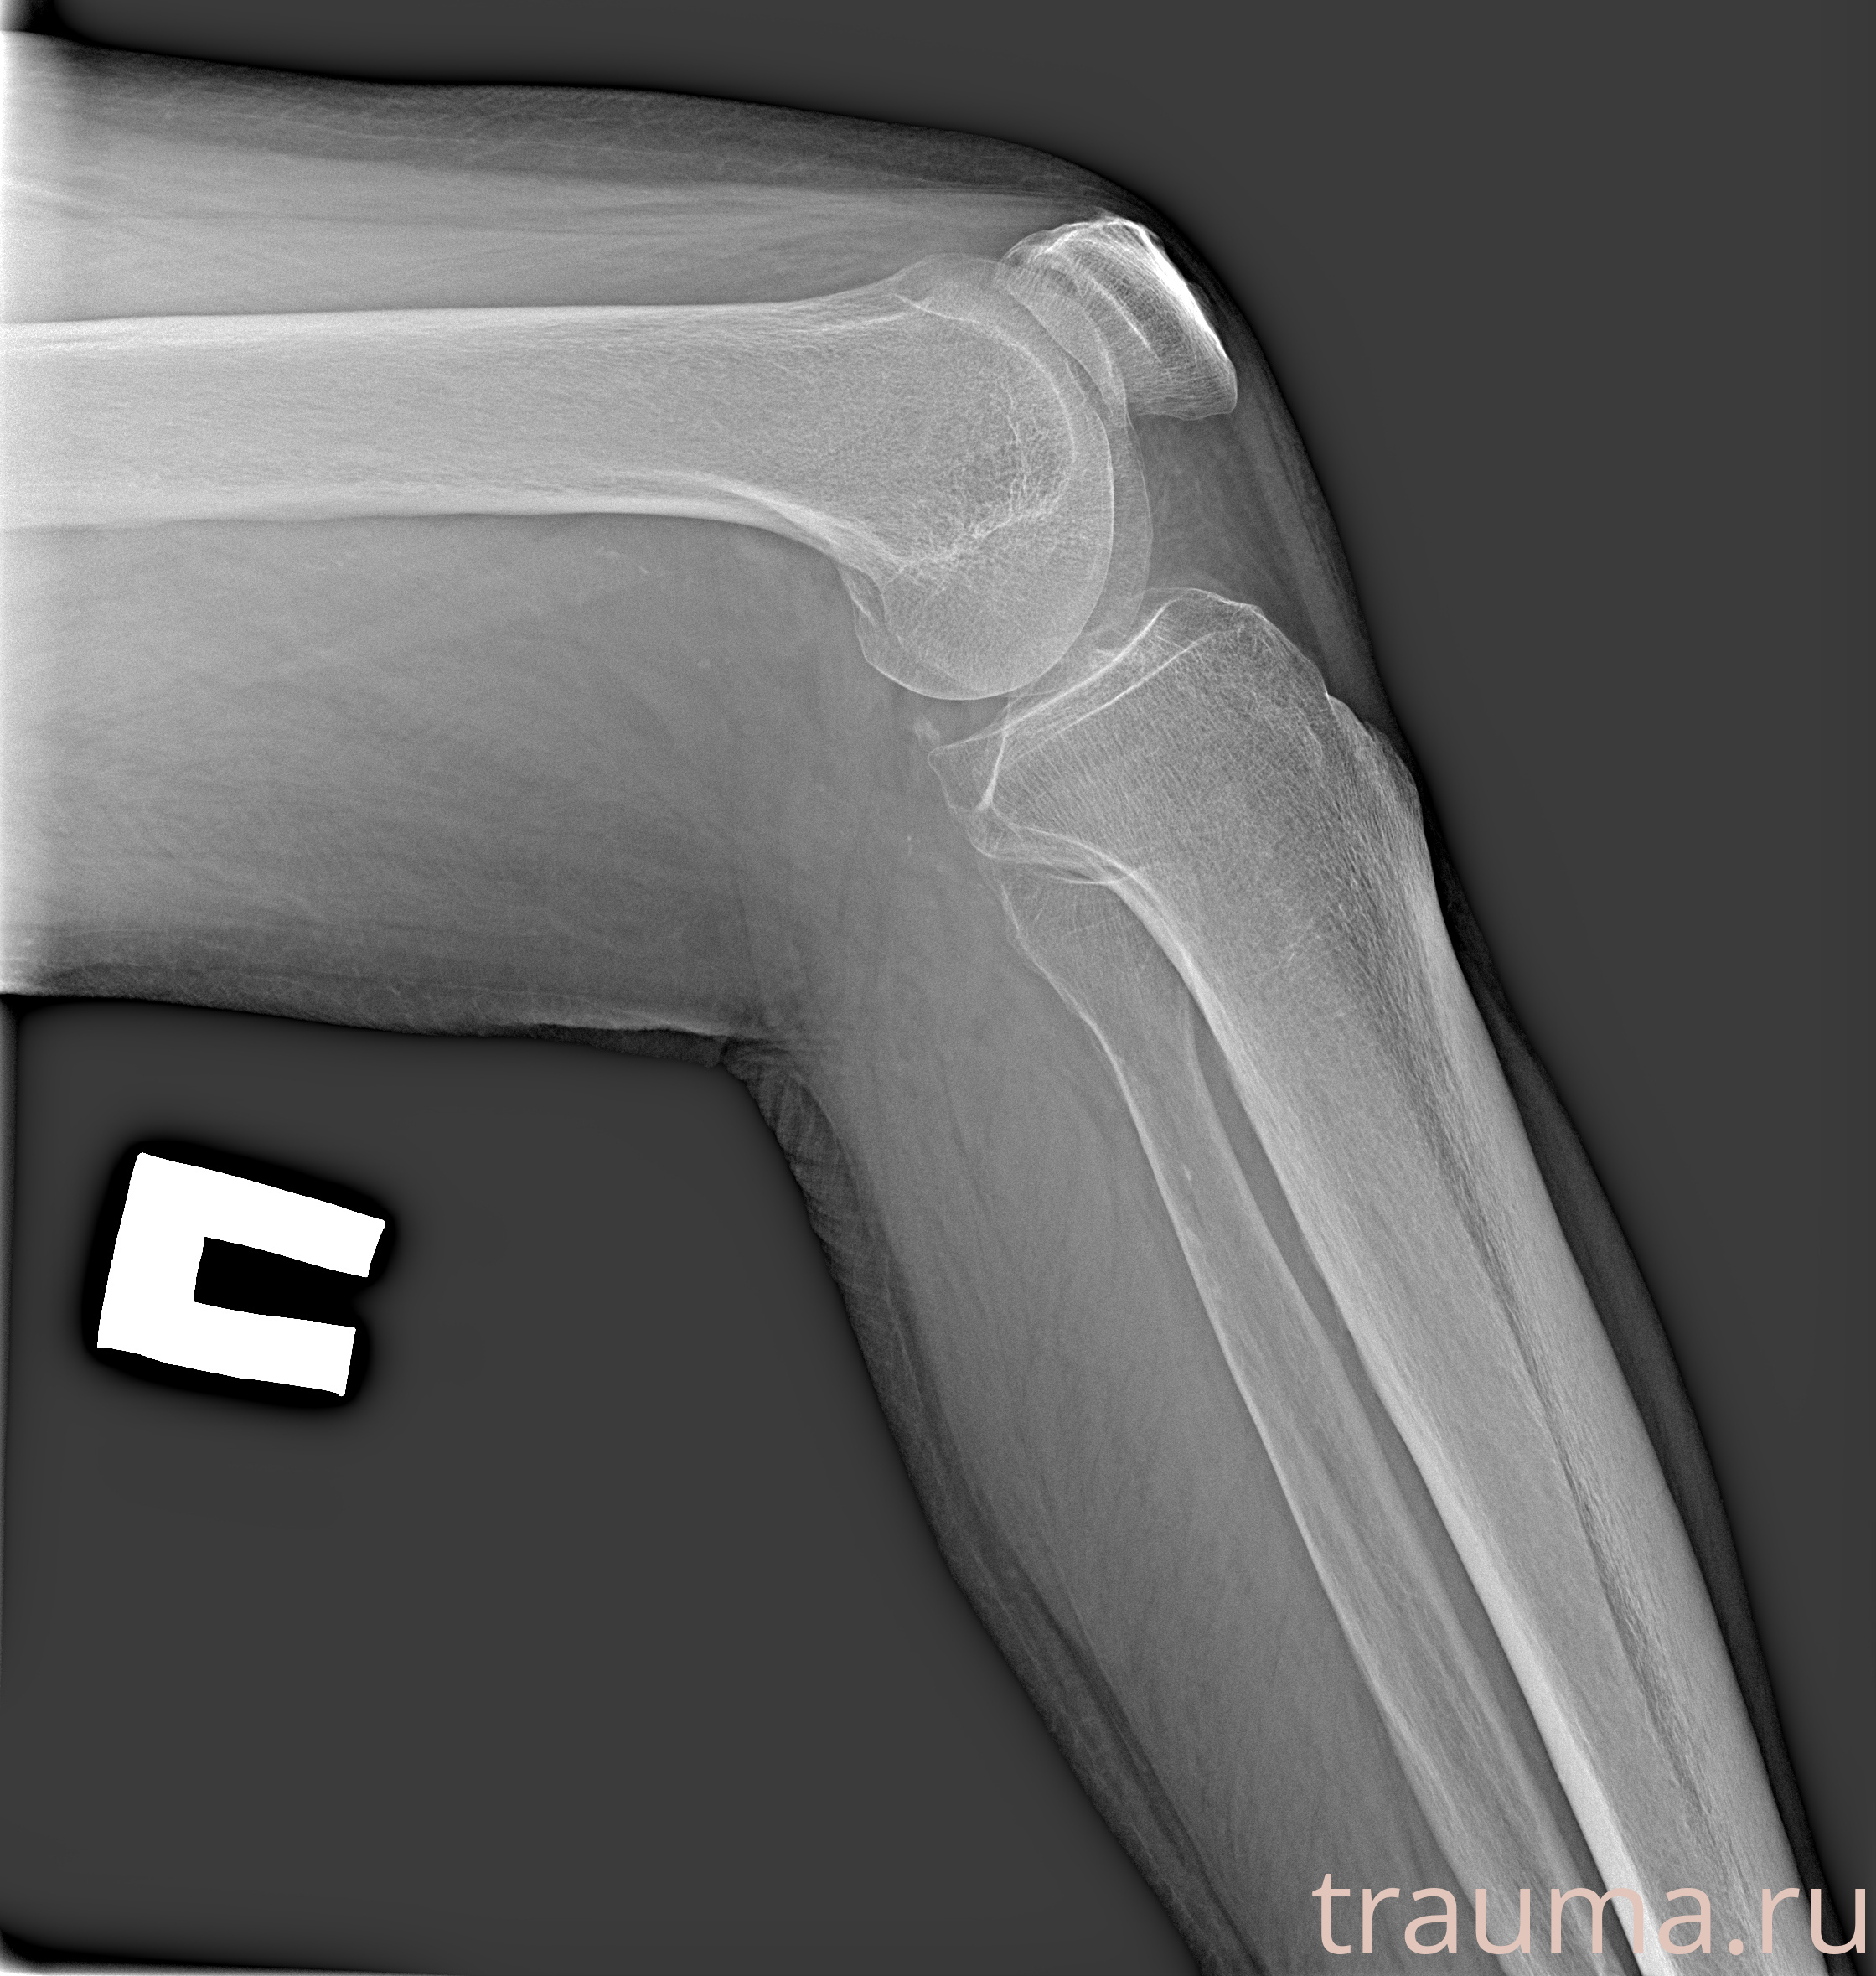

Рентгенограммы